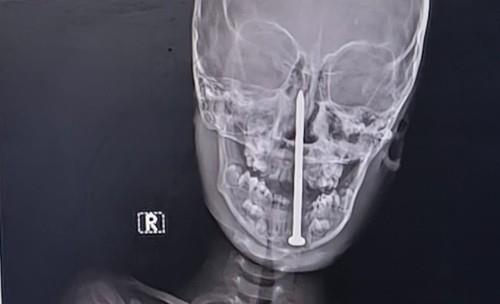

Dečaku se tokom igranja ekser od 8 cm zabio u glavu: Lekari se smrznuli kad su videli snimak, ono što je potom usledilo je čudo (FOTO)

dečak ekser profimedia-1005204043.jpg

3 / 4

TIM / Jam Press / Profimedia